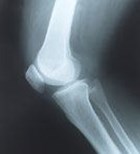

מפרק הברך הוא העמוס והמורכב בשלד וחשוף לפגיעות, כגון קרע...

מפרק הברך נחשב "מועד לפורענות" - בכל הגילאים והמגזרים....

שלום רב לרוב בשחיקה של מפרק הברך טווחי התנועה מוגבלים עקב הוצרות של זיזי עצם אשר מטרתם לפזר את העומסים המופעלים על המפרק על ידי יצירת שטח פנים גדול יותר , זיזי העצם הללו גם אחראים לכך שטווחי תנועה מוגבלים הם, ביחד עם זאת בתהליך שחיקה של מפרק הברך ישנם גם דברים מכניים אשר יכולים במפרק ולשבש את טווחי התנועה ךרוב ניתן לטפל בזה בארתרוסקופיה אך ארתרוסקופיה שהיא גישה מזערית (ניקיון הברך) לא תפתור את שחיקת הסחוס בברכה ד"ר בנימין בנדר www.drbender.co.il

בוקר טוב כאבים בברך יכולים לנבוע ממספר רב של גורמים , רק בחלק ארטרוסקופיה יכולה לעזור , לעיתים לא נדרש טיפול ניתוחי ולעיתים כן . הדיון איזה טיפול מתאים לאחר כשלון של טיפול ארטרוסקופי הינו מורכב ודורש תשאול מעמיק בדיקה גופנית יסודית ומעבר על הדמייה כולל דוח ניתוח ארטרוסקופי. ממליץ פניה למומחה ברך ( במידה ואתה מעוניין אשמח לעזור , בברכה ) ד"ר נמרוד שניר מומחה לכירורגיה אורטופדיה ניתוחי החלפות מפרקים , ניתוחים ארטרוסקופיים ורפואת ספורט מנהל היחידה להחלפות מפרקים (ברך וירך) המרכז הרפואי תל אביב, ישראל